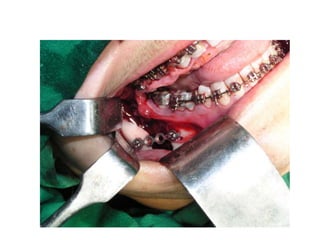

Orthognathic Surgical procedures

• Sagittal procedures

• Transverse procedures

• Vertical procedures